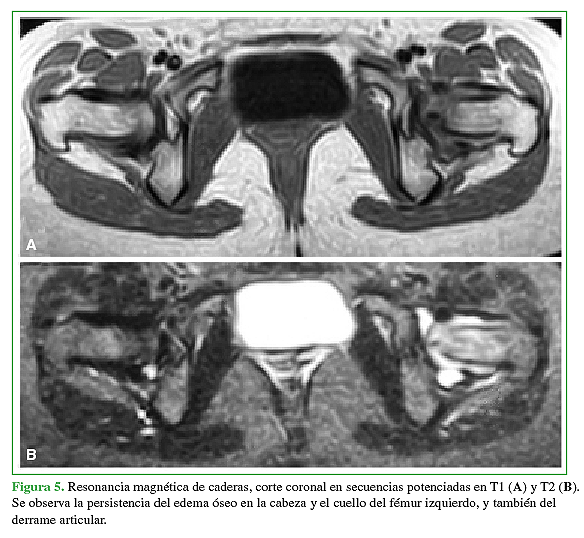

Acceso mediante suscripción PDF Acceso mediante suscripción PDF_EN (English) Acceso mediante suscripción Figura 1 Acceso mediante suscripción Figura 2 Acceso mediante suscripción Figura 3 Acceso mediante suscripción Figura 4 Acceso mediante suscripción Figura 5 Acceso mediante suscripción Figura 6 Acceso mediante suscripción HTML